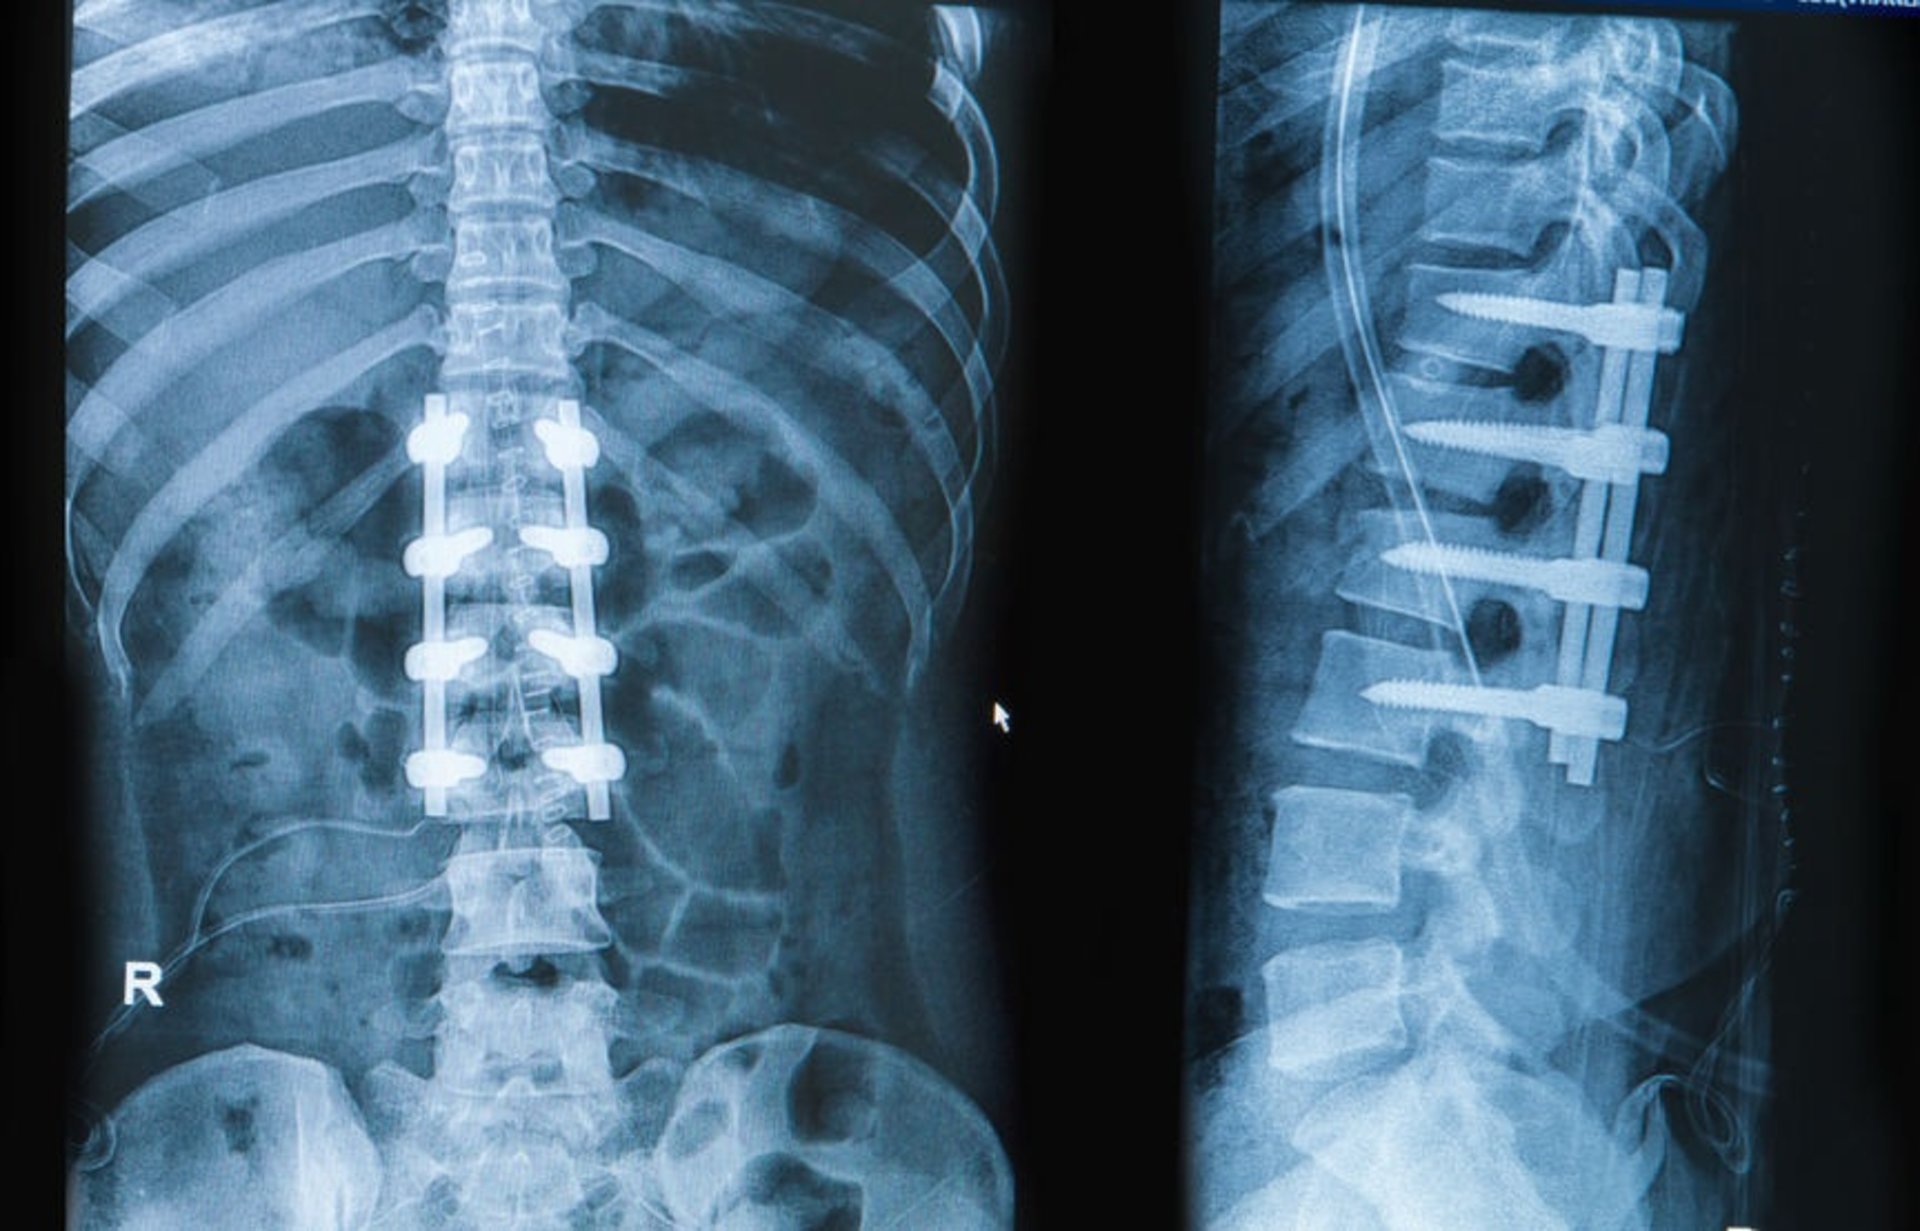

The treatment is performed using advanced tools and imaging guidance. Small incisions are made, and specialized instruments are used to stabilize the spine with screws, rods, or bone grafts. This ensures proper alignment while minimizing trauma to the body.